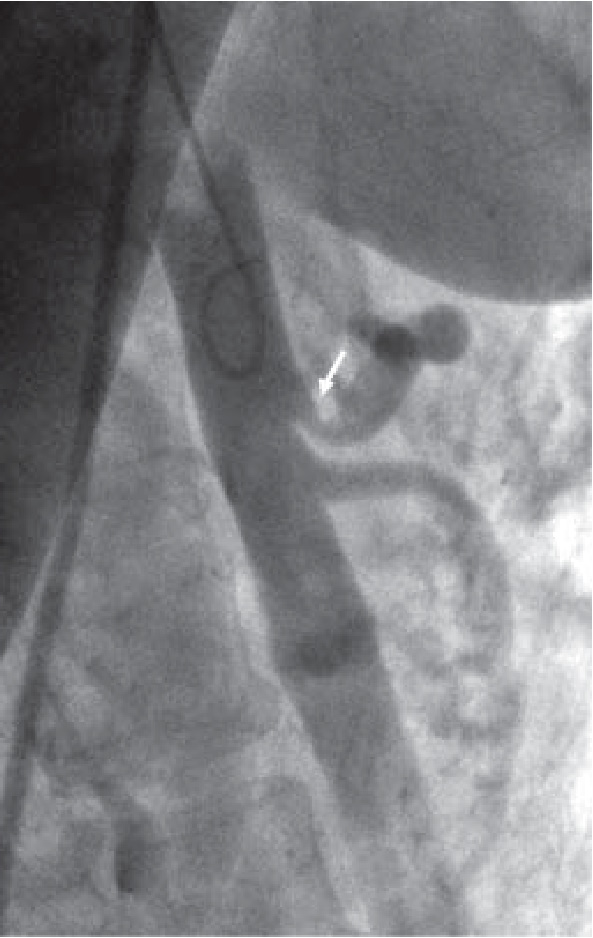

Дальнейшее длительное динамическое наблюдение больной показало отчетливую положительную динамику заболевания. После оперативного вмешательства абдоминально-болевой синдром и синкопальные состояния не рецидивировали, полный регресс нейровегетативных симптомов (эпизодов внезапной слабости, головокружений, повышений температуры тела, ознобов, потливости, чувства нехватки воздуха при бытовых нагрузках, сердцебиений, суставных болей) отмечен через 4 месяца после операции. В период последней госпитализации в сентябре 2018 г. жалоб не предъявляла. Объективно со стороны внутренних органов патологических отклонений не выявлено. При аускультации систолический шум в эпигастрии не выслушивается. Настроение ровное. Позитивно настроена на будущее. Неврологический статус без особенностей. На выполненной КТ-ангиографии патологии со стороны брюшной аорты и ее непарных висцеральных ветвей не выявлено (рис. 3).

Рис. 3. КТ-ангиография брюшной аорты от 28.09.2018 г. Брюшной отдел аорты и непарные висцеральные артерии без патологических изменений